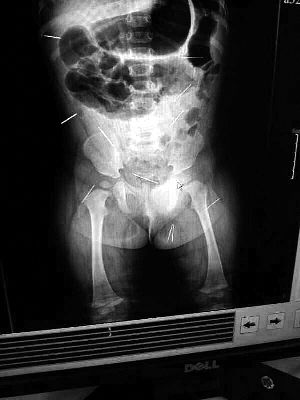

山東聊城11個(gè)月女嬰萱萱(化名)疑似被人以12根鋼針插滿臀部、腹腔等部位,昨天在兒童醫(yī)院會診后,醫(yī)生稱3根針靠近胸腔最危險(xiǎn),首批先行取出,預(yù)計(jì)將在下周二手術(shù)。孩子父母稱孩子一直由家人照顧,自家與他人并無冤怨。山東警方表示正在偵破中,不便透露案情。

“要不是當(dāng)初那幾個(gè)紅點(diǎn),可能到現(xiàn)在我們還不知道孩子身體里有鋼針!”昨天,在兒童醫(yī)院住院處,萱萱爸爸范先生稱,日前原本很愛笑的萱萱突然變得有些焦躁,一抱起來就哭,孩子母親偶然間在萱萱屁股上發(fā)現(xiàn)了幾個(gè)小紅點(diǎn)兒,原以為是蚊蟲叮咬,就醫(yī)結(jié)果卻讓人不寒而栗?!搬t(yī)院拍出的片子上,萱萱的體內(nèi)有12根鋼針,插滿臀部、腹腔、骨盆等各個(gè)部位。”范先生介紹,因?yàn)殇撫樢焉钊塍w內(nèi),要是孩子不哭鬧,他們很難發(fā)現(xiàn)。

北京晨報(bào)記者了解到,目前體內(nèi)的12根鋼針多分布在孩子的臀部,一根在腹部,其余3根在胸腔附近,其中一根很接近心臟。“因?yàn)楹⒆犹?,醫(yī)生們害怕取針的時(shí)候?qū)λ斐蓚?,在胸腔附近?針可能會威脅她的生命”。